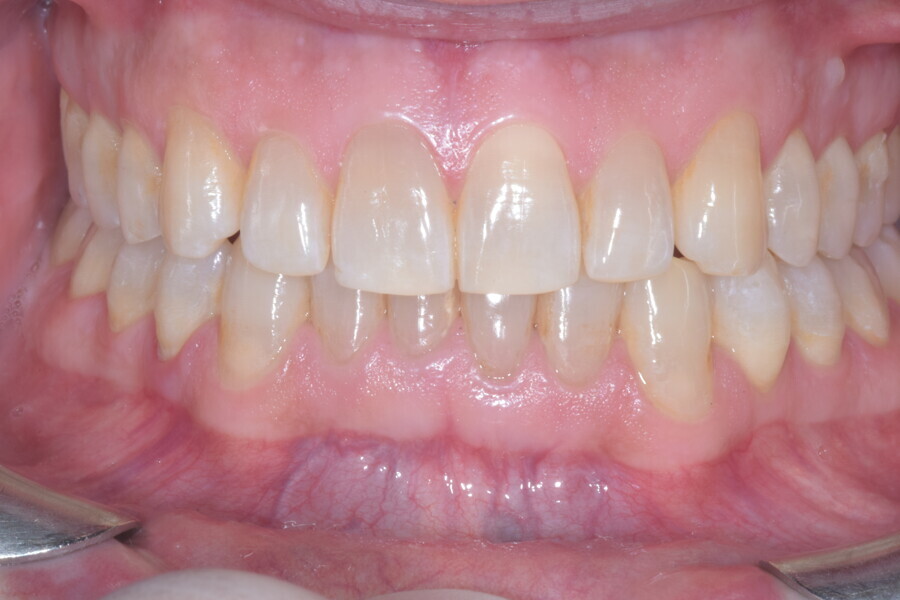

En raison de l’âge du patient, les aligneurs ont été changés tous les dix jours, dans le cadre d’un traitement d’une durée inférieure à six mois. À la fin de la première série d’aligneurs, un nouveau plan de traitement numérique comportant cinq autres aligneurs a été conçu, en vue d’améliorer l’intercuspidation des molaires sans élastiques. (Photos : Dr Alessandro Greco)

Le plan de traitement numérique (ClinCheck) avait prévu douze aligneurs pour l’arcade maxillaire et dix-sept pour l’arcade mandibulaire. Les objectifs du traitement visaient à combiner les mouvements verticaux d’extrusion des dents postérieures et les mouvements d’intrusion des dents antérieurs, au moyen de rampes d’occlusion, tout en utilisant des taquets d’extrusion pour assurer la désocclusion des dents postérieures et l’intrusion des dents antérieures inférieures, nécessaires au nivellement de l’arcade mandibulaire. La courbe de Spee a été nivelée et le profil plat ainsi que la position des lèvres ont été améliorés par une vestibulo-version des incisives supérieures et inférieures. Le plan avait prévu des élastiques de classe II pour faciliter la vestibulo-version des dents inférieures et les puissants contacts occlusaux postérieurs, avec une extrusion relative des dents postérieures. Une morphologie plus large de l’arcade et une intercuspidation idéale ont été obtenues par des mouvements de torque proches de 0° des dents latérales et postérieures supérieures. Aucune conception technique excessive n’avait été prévue dans le plan de traitement numérique. En raison de l’âge du patient, les aligneurs ont été changés tous les dix jours, dans le cadre d’un traitement d’une durée inférieure à six mois. À la fin de la première série d’aligneurs (Figs. 20–24), un nouveau plan de traitement numérique comportant cinq autres aligneurs a été conçu, en vue d’améliorer l’intercuspidation des molaires sans élastiques. La durée totale du traitement a donc été prolongée jusqu’à 7,5 mois puisque les aligneurs supplémentaires étaient changés toutes les semaines.

À la fin du traitement, on pouvait observer une relation de classe I des canines et des molaires, une légère augmentation de l’inclinaison des incisives supérieures (Ui-FH = 112°), une correction complète de l’inclinaison des incisives inférieures (IMPA = 97,09°) grâce à la vestibulo-version, et une légère amélioration de l’hypodivergence (SN-GoGn = 27°) résultant de l’extrusion relative des dents postérieures, et de l’utilisation d’élastiques de classe II — petite variation (1°) très intéressante compte tenu de l’âge du patient (Figs. 25–35). La ligne du sourire était harmonieuse et correspondait à une relation idéale entre les incisives supérieures et la lèvre inférieure. Le sourire avait été élargi grâce au contrôle du torque des segments latéraux et postérieurs.

Lors du suivi à un an, alors que le patient portait un appareil de rétention (appareil de rétention Vivera avec rampes d’occlusion, Align Technology), le résultat était stable et l’intercuspation était nettement meilleure (Figs. 38–42).